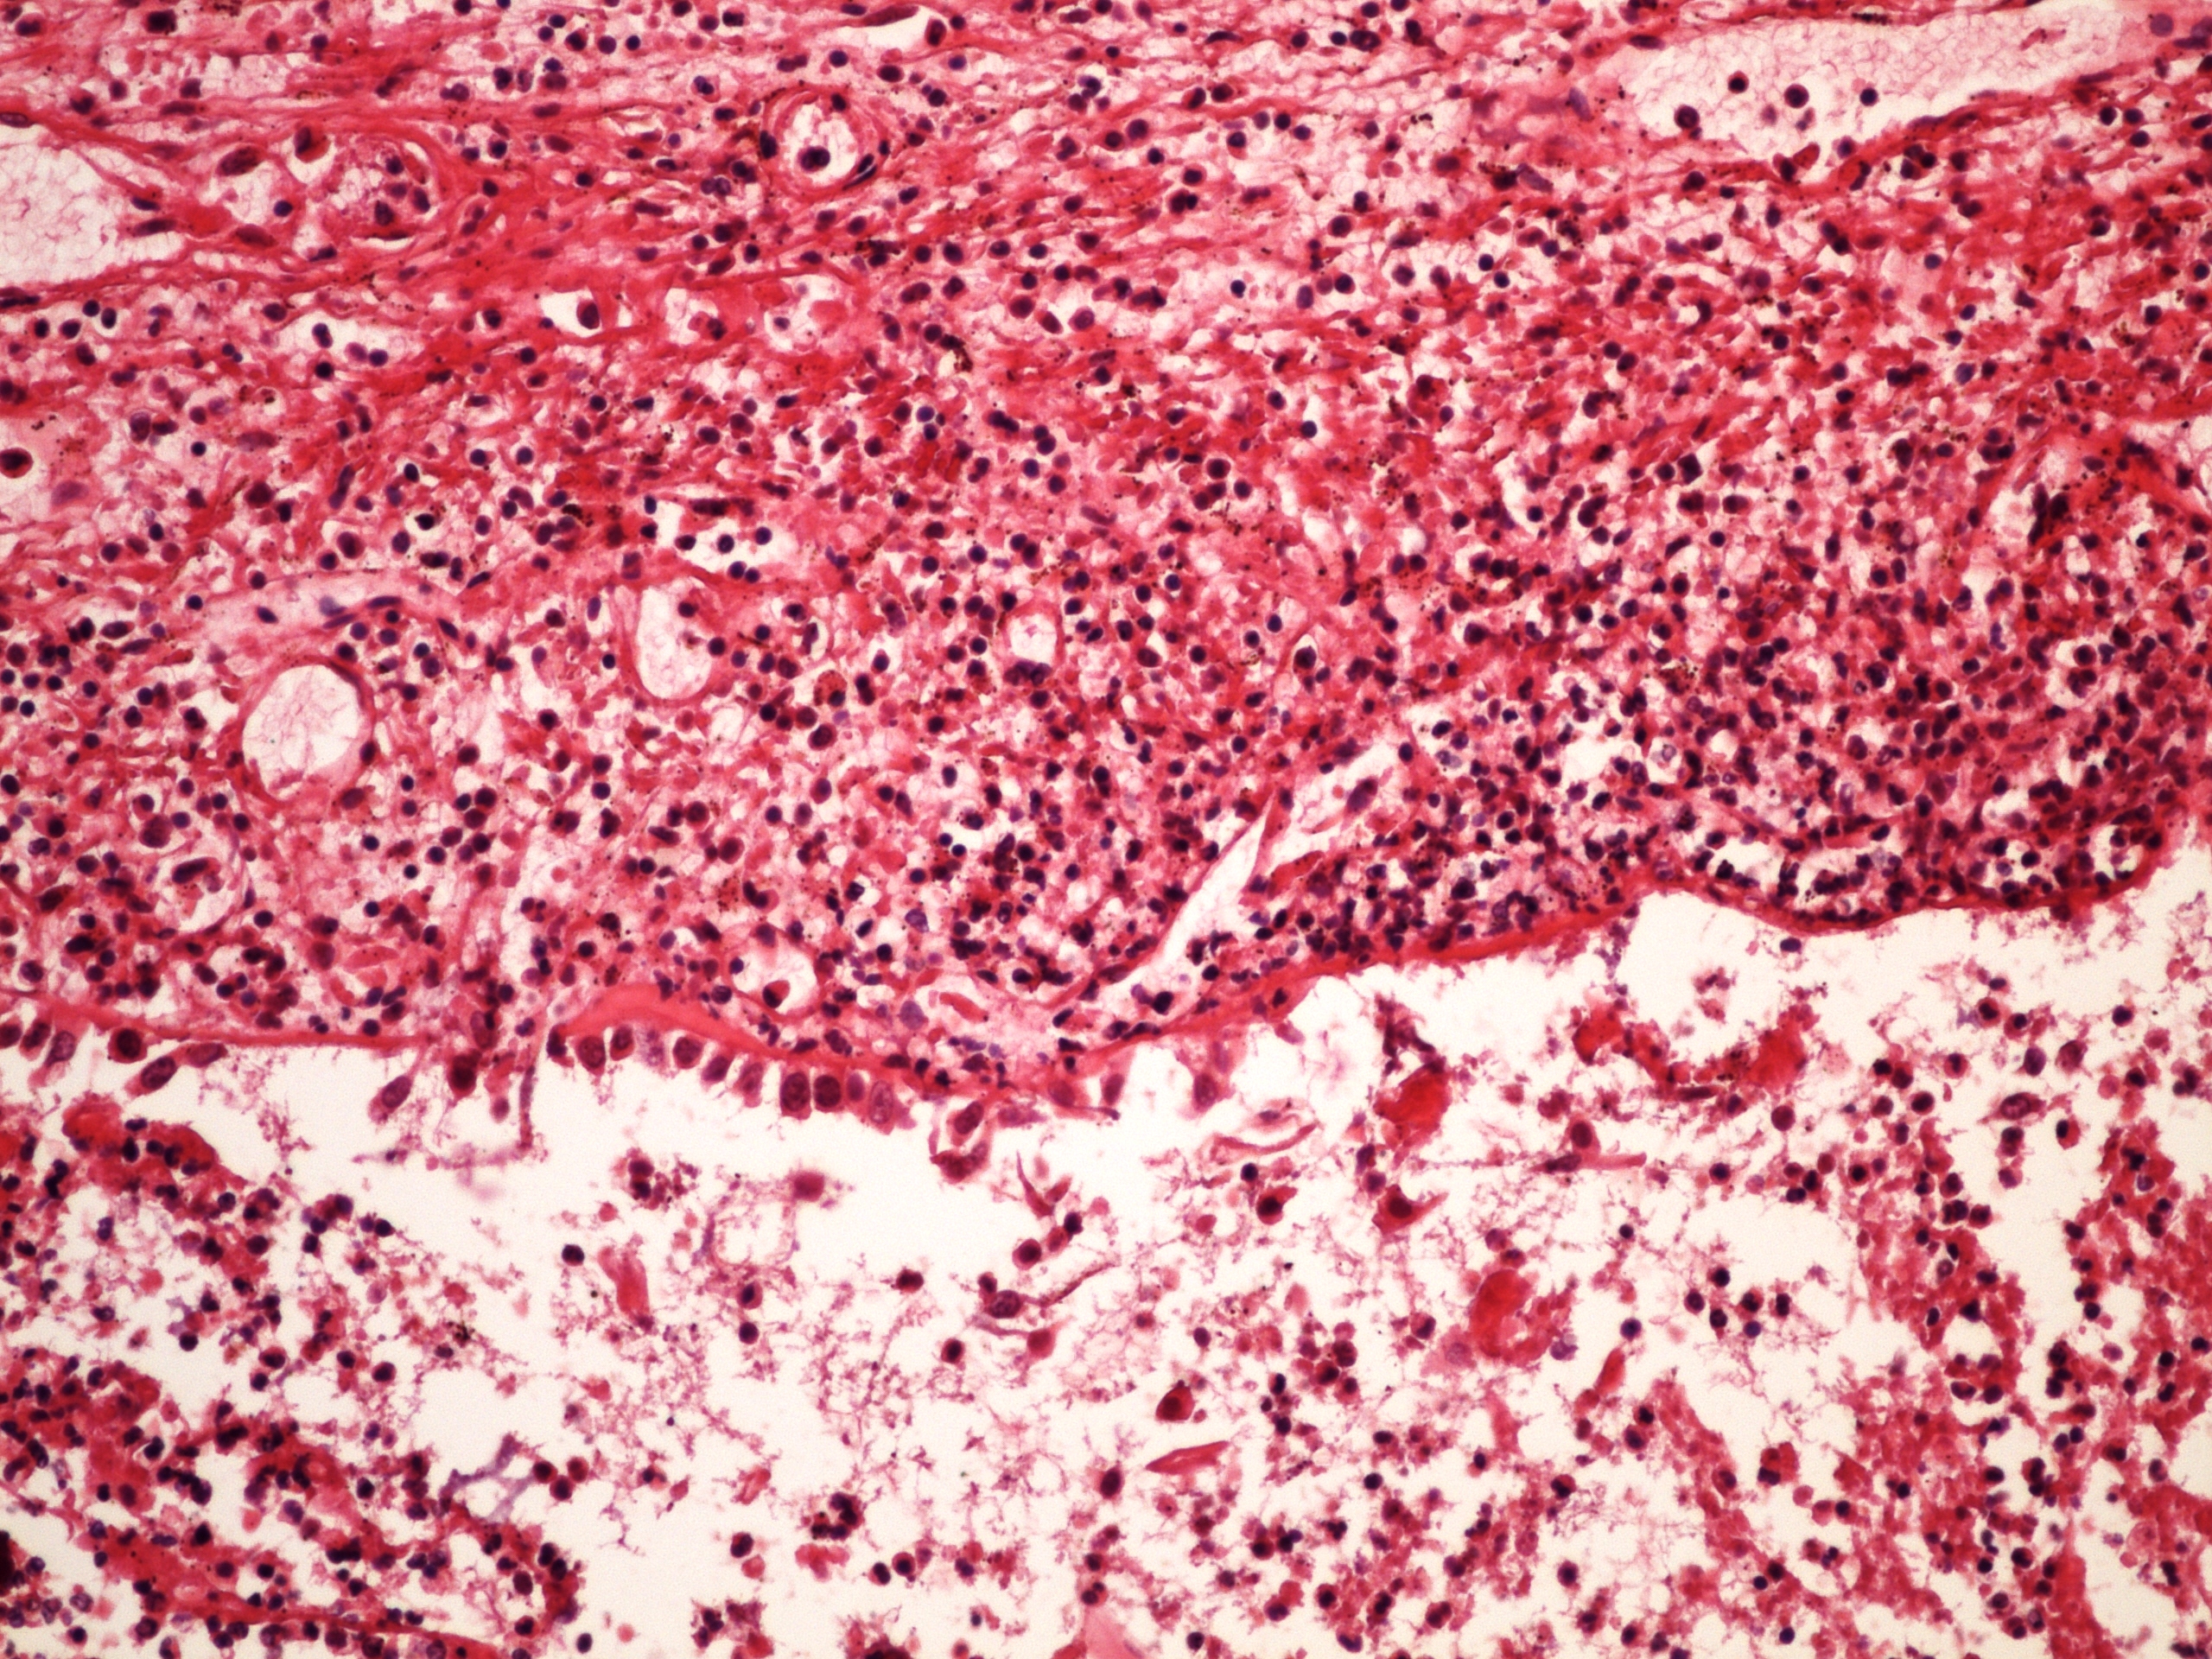

Preparát č.5 a č.6 - hnisavá leptomeningitida

Struktury

- mozek

- mozkové obaly

- zánětlivý infiltrát